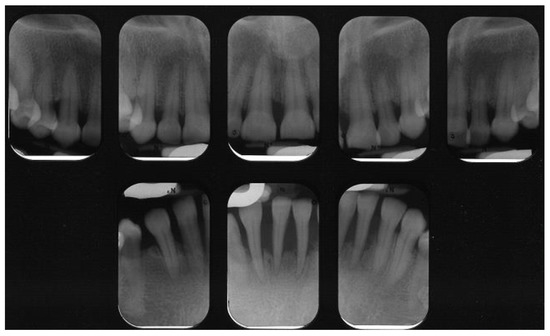

1. Overview—Periodontal Disease Etiology and Pathogenesis

2.2. Necrotizing Periodontal Diseases (NPDs)

2.3. Periodontitis as a Manifestation of Systemic Diseases

2.3.1. Down Syndrome

2.3.2. Human Immunodeficiency Virus (HIV)

2.3.3. Rheumatoid Arthritis (RA)

2.4. Systemic Diseases or Conditions Affecting the Periodontal Supporting Tissues